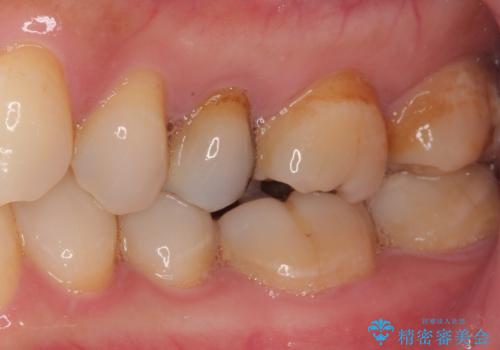

オールセラミッククラウンによる奥歯のむし歯治療

やはりむし歯は大きく、一部歯髄を切除することとなりましたが、その後は良好な経過をたどっています。